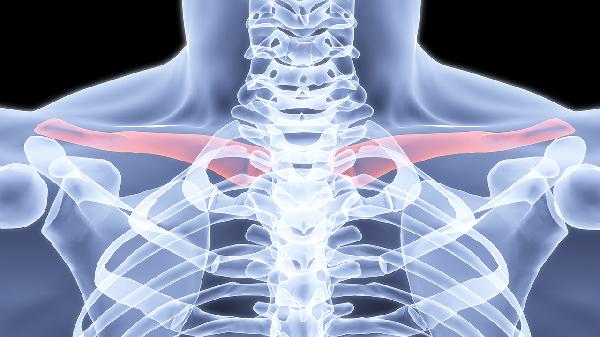

当出现骨折端分离超过2厘米、皮肤即将穿透、血管神经损伤等绝对手术指征时,需行切开复位内固定术。常用术式包括解剖型锁骨钢板固定或弹性髓内钉固定。术后早期开始被动关节活动,6周后逐步过渡到抗阻力训练,通常3个月可恢复日常活动。